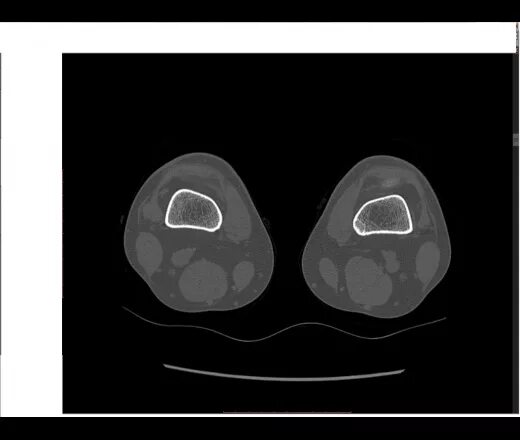

Фиброма кт